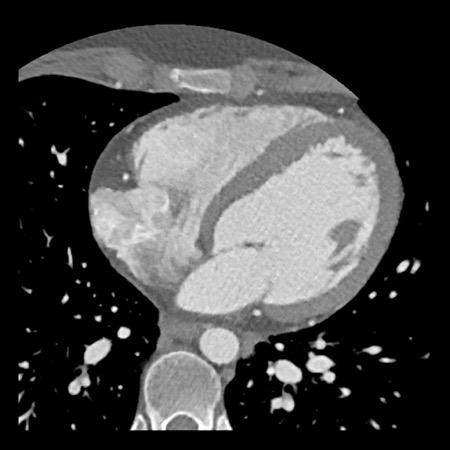

case 1 – CAD-RADS 2/P1

First, scroll through the scan.

Not all images are included. Some images without any abnormalities are skipped

from the series.

How would you describe the findings on the coronary CTA?

The findings are:

- Agatston score of

this patient was 14 (P1). Please, also note the calcification of the aortic valve. - Some partially

calcified and calcified plaques are present in the LAD with mild stenosis

(25-49%). - Calcified-plaque in

the LCX causing minimal stenosis (<25%). - Non-calcified

plaque in the distal RCA causing minimal stenosis (<25%). - This patient classifies

as CAD-RADS 2/P1, which means no further workup is needed.